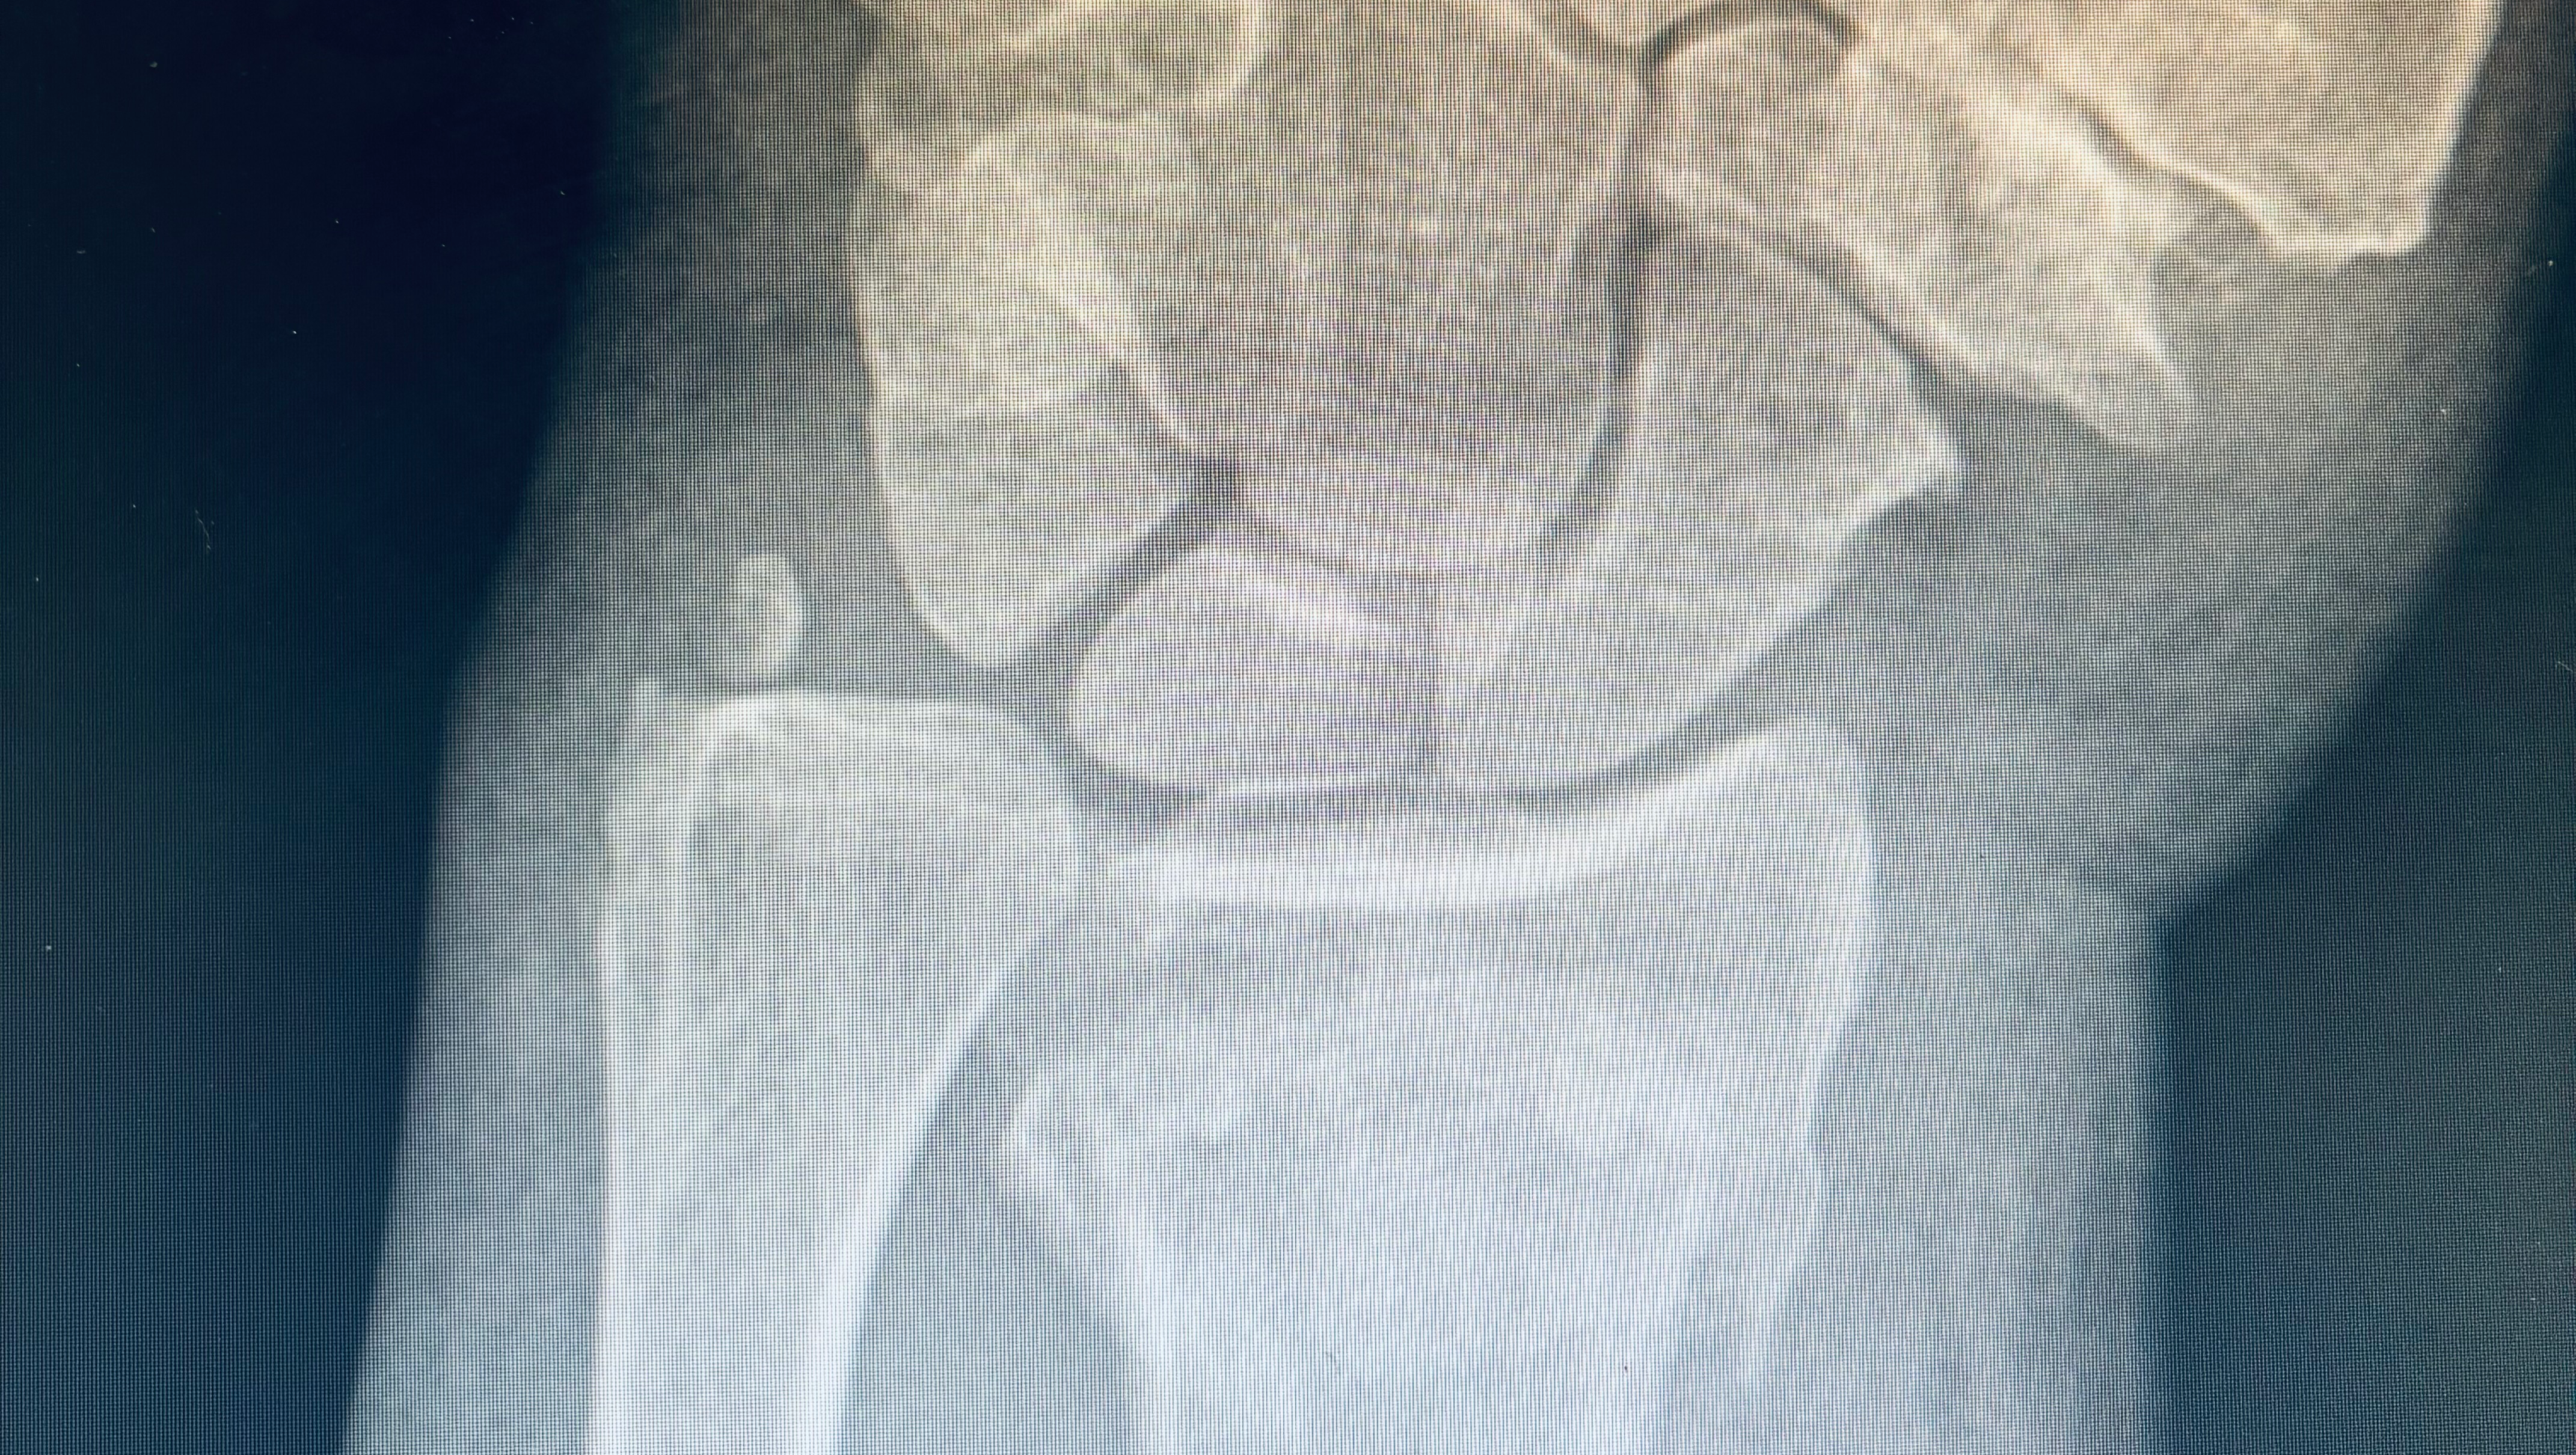

We are asking everyone to come together in support of Denise, “Socks” as she takes several weeks off to recover after surgery to repair her broken wrist. Socks has been a blessing in so many lives, always there to lend a hand or ear to everyone around her who might be in need. We all pray we can come together to help take some of the burden/stressors off her shoulders so she is able to fully recover and come back to Jimmy’s when she is ready.